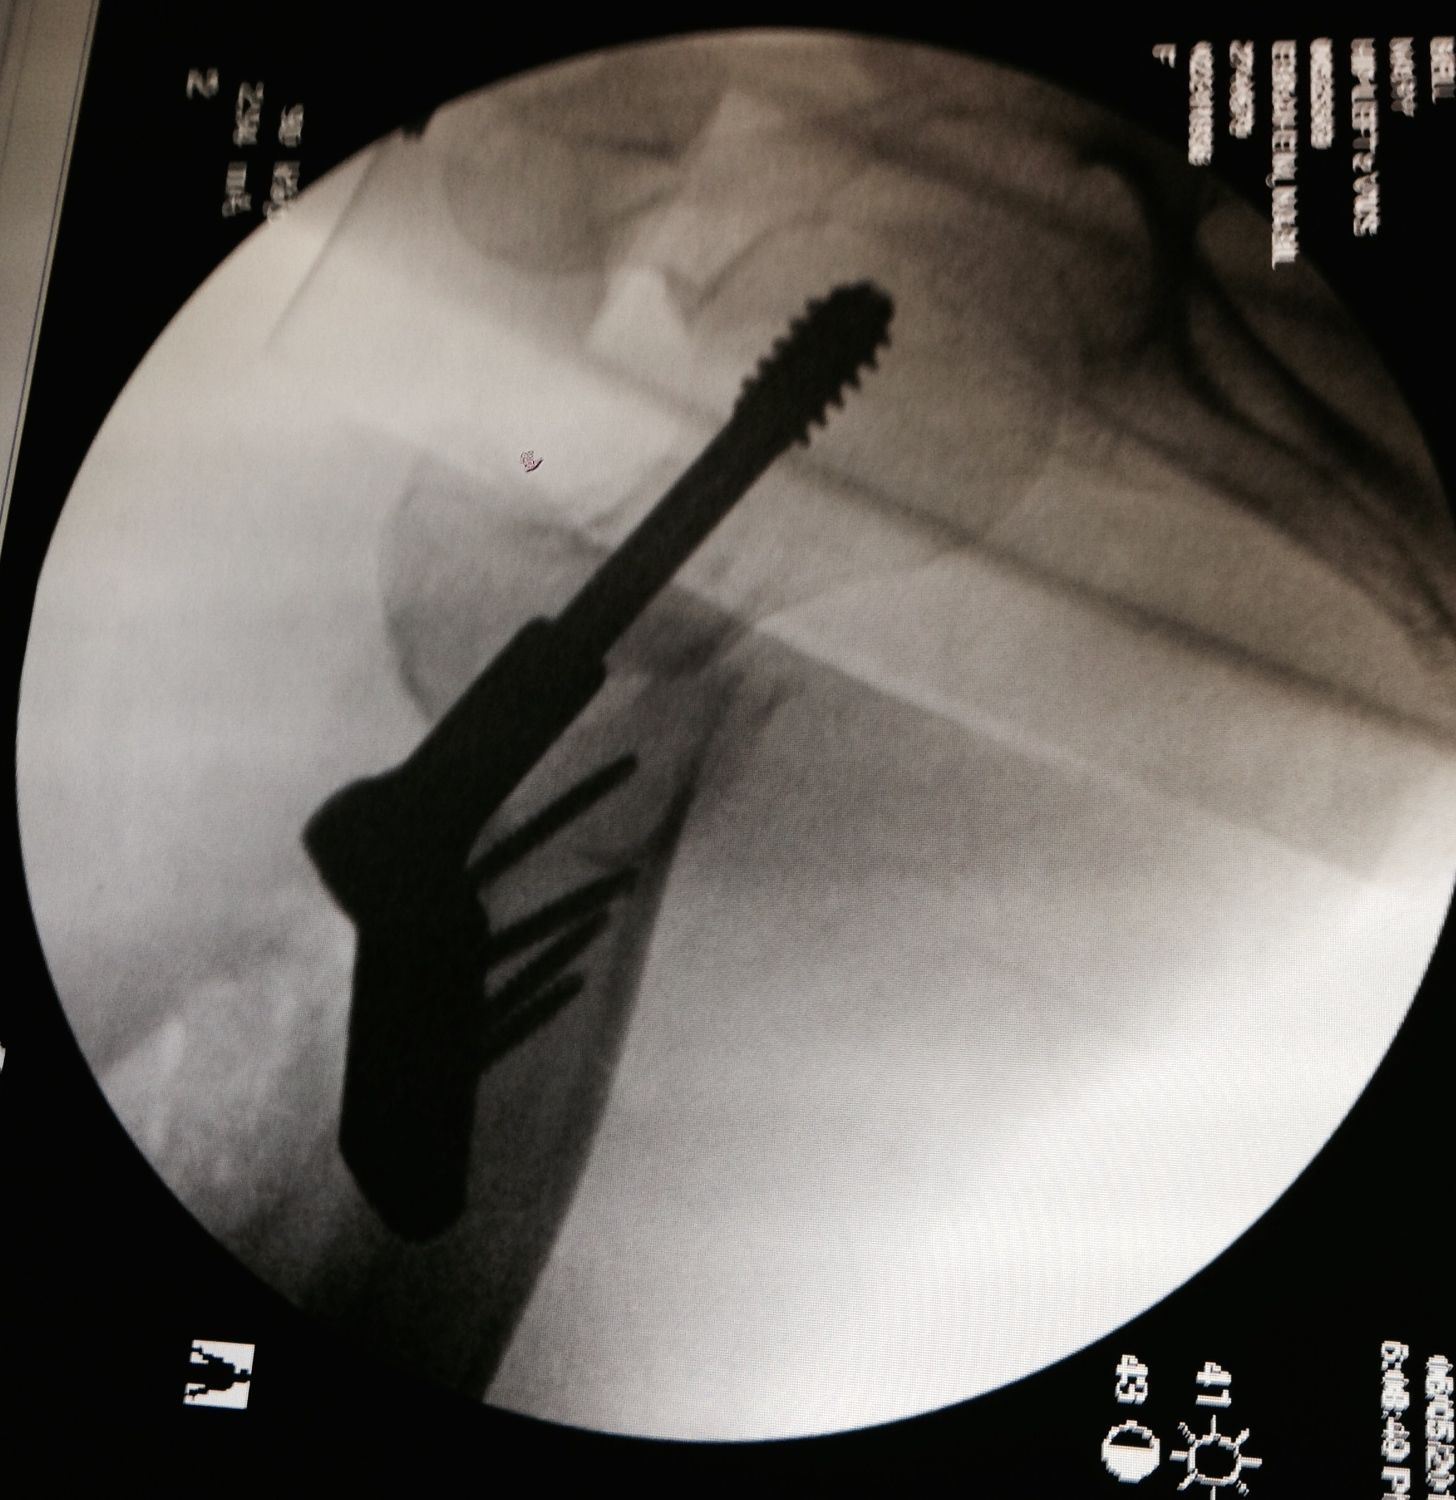

| Fractured Hip After Repair |

I should begin by clarifying that Nina’s post All About Hip Replacements and Yoga was specifically looking at the use of yoga for total hip replacements, which are usually elective procedures done mostly for those with severe arthritis of the hip joint. Our writer is in a different boat, having apparently suffered a recent hip fracture, presumably following a fall of some sort. In the face of acute trauma such as this, there are any number of possible ways an orthopedic surgeon might repair a fractured hip, depending on where the break is on the thigh bone and whether the bones are lined up or displaced. For example, my mother fell and broke her thigh bone a few years back while gardening, and because of the location of the break and the offset alignment of the two parts of the bone, a metal rod with teeth—which looked like a comb with only five teeth—was used to keep the two parts of her femur bone together as they healed. So, no total hip replacement for my mom, either! However, she still started limited physical therapy shortly after her surgery, which progressed in challenge as her pain subsided and she began to get stronger.